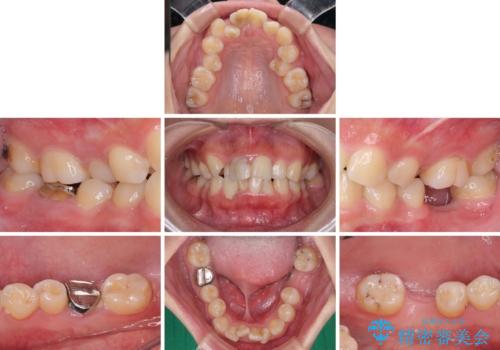

- 放置した虫歯や抜いたままの奥歯、前歯のデコボコを気にして来院された患者様です。

口元の突出感は少なく、下顎の叢生は軽微なものであったので、叢生の強い上顎左右の小臼歯を1本ずつ抜歯し、ワイヤー装置にて矯正治療を行うこととしました。

矯正治療を行う前に、根管治療の必要な上顎前歯と下顎大臼歯の根管治療を行い、矯正治療の途中で下顎の欠損部にインプラント埋入することとし、矯正治療後に補綴治療を行うこととしました。

矯正治療をしたいと思っていたが、放置している虫歯が多いため、どこに相談に行けば良いのか分からずにいたそうですが、当院の総合歯科診療を見て来院されたそうです。

矯正治療中にインプラント埋入を行うなど、余計な時間や無駄のない治療を行うことができました。